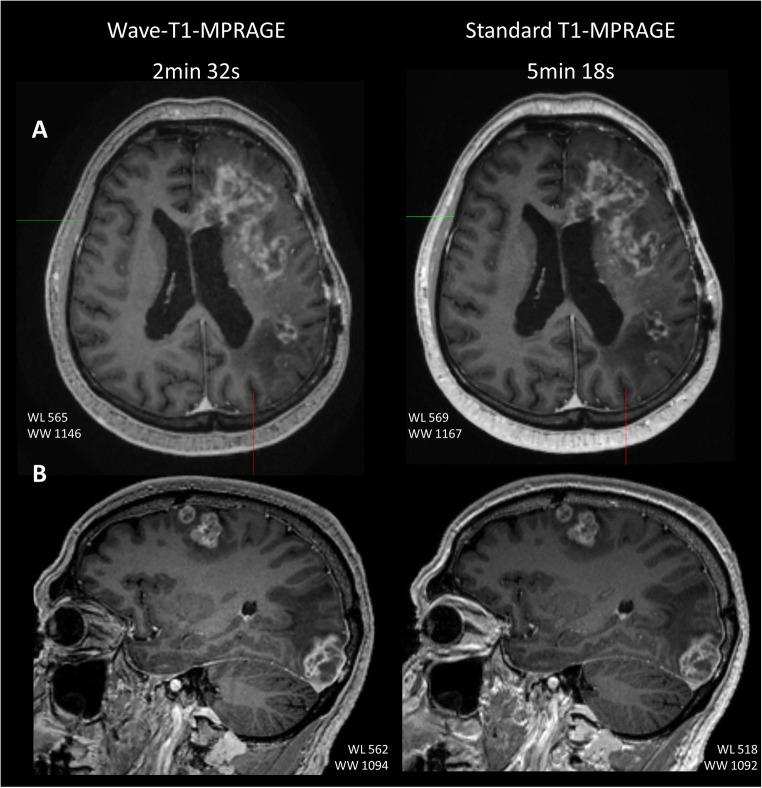

This study included 80 patients undergoing contrast-enhanced brain MRI. The participants were scanned with a standard post-contrast T1-MPRAGE sequence (acceleration factor [R] = 2 using GRAPPA parallel imaging technique, acquisition time [TA] = 5 min 18 s) and a prototype post-contrast Wave-T1-MPRAGE sequence (R = 4, TA = 2 min 32 s). Two neuroradiologists performed a head-to-head evaluation of both sequences and rated the visualization of enhancement, sharpness, noise, motion artifacts, and overall diagnostic quality. A 15% noninferiority margin was used to test whether post-contrast Wave-T1-MPRAGE was noninferior to standard T1-MPRAGE. Inter-rater and intra-rater agreement were calculated. Quantitative assessment of CNR/SNR was performed.

Wave-T1-MPRAGE was noninferior to standard T1-MPRAGE for delineating enhancing lesions with unanimous agreement in all cases between raters. Wave-T1-MPRAGE was noninferior in the perception of noise (p < 0.001), motion artifact (p < 0.001), and overall diagnostic quality (p < 0.001).

High-accelerated post-contrast Wave-T1-MPRAGE enabled a two-fold reduction in acquisition time compared to the standard sequence with comparable performance for visualization of enhancing pathology and equivalent perception of noise, motion artifacts and overall diagnostic quality without loss of clinically important information.

• Post-contrast wave-controlled aliasing in parallel imaging (CAIPI) T1-MPRAGE accelerated the acquisition of three-dimensional (3D) high-resolution post-contrast images by more than two-fold. • Post-contrast Wave-T1-MPRAGE was noninferior to standard T1-MPRAGE with unanimous agreement between reviewers (100% in 80 cases) for the visualization of intracranial enhancing lesions. • Wave-T1-MPRAGE was equivalent to the standard sequence in the perception of noise in 94% (75 of 80) of cases and was preferred in 16% (13 of 80) of cases for decreased motion artifact.